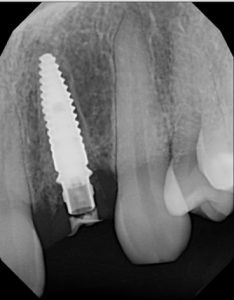

This video demonstrates immediate implant placement in the esthetic zone following atraumatic extraction of a lateral incisor. Emphasis is placed on preserving the hard and soft tissue architecture critical for predictable esthetic outcomes.

The procedure is presented step by step, including minimally traumatic extraction techniques, immediate implant placement, and fabrication and placement of a customized healing abutment to support peri-implant soft tissue contours. Clinical principles for maintaining papillae, controlling the emergence profile, and optimizing soft tissue healing are highlighted.